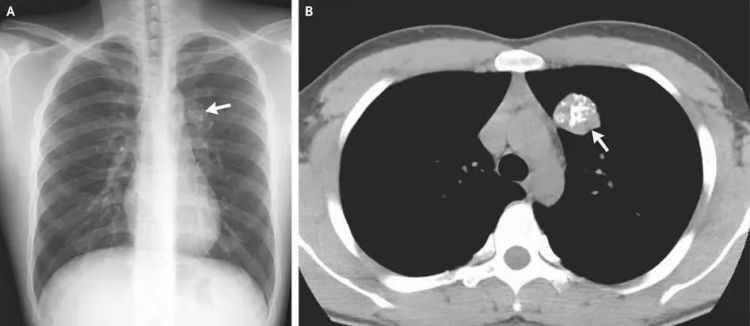

事实上,在X线片、CT、钼靶、超声报告中,常常会出现“钙化”“钙化灶”的字样。

肺部钙化:一般来说,肺部的单个或少量钙化灶多为陈旧性病变遗留,通常无需特殊治疗,定期复查观察即可。但如果钙化灶较大或数量较多,伴有其他异常表现,如咳嗽、咳痰、咯血、胸痛等,则需要进一步检查。